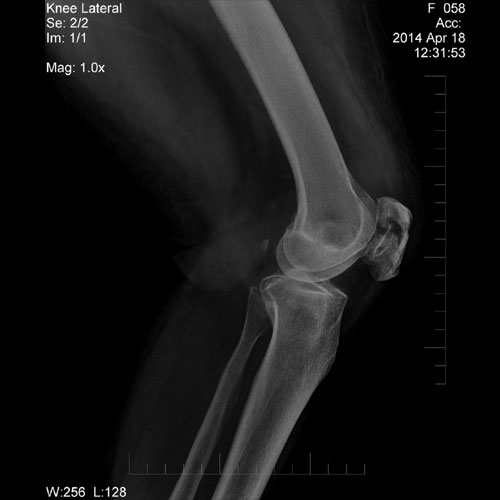

54 year old female with h/o injury; X-Ray of knee joint shows fracture at patella.